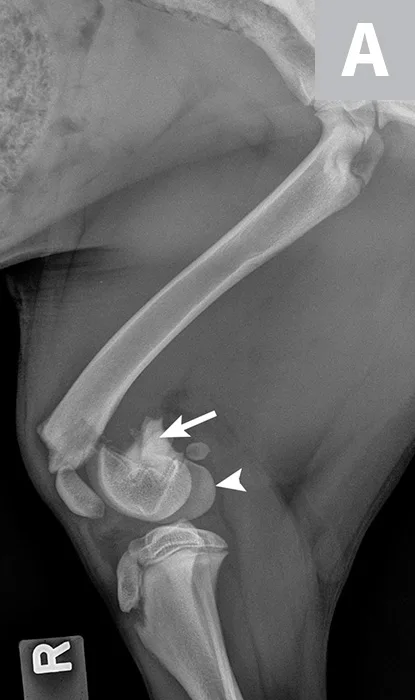

At the 5-week postoperative examination, Maggie was fully weight-bearing on her right pelvic limb and the stifle had full and pain-free range of motion. Radiography of the stifle revealed that the fracture was healed, the implants were stable, and the distal femoral physis was closed (Figure 3). A closed distal femoral physis is a common finding after fracture repair, as the germinal cells, which are responsible for physis growth, are frequently irreversibly damaged during the fracture event. Premature physeal closure can result in shortening of the femur, particularly if the animal is young and has large remaining growth potential.2,10 However, a closed distal femoral physis in a dog of Maggie’s age does not usually result in a clinical problem, as dogs are generally able to compensate for mild limb length discrepancies through extension of adjacent joints and compensatory overgrowth of the tibia.2,10

Figure 3

Lateral (A) and craniocaudal (B) radiographs of the femur 5 weeks after fracture repair. The fracture has healed and the distal femoral physis has closed.